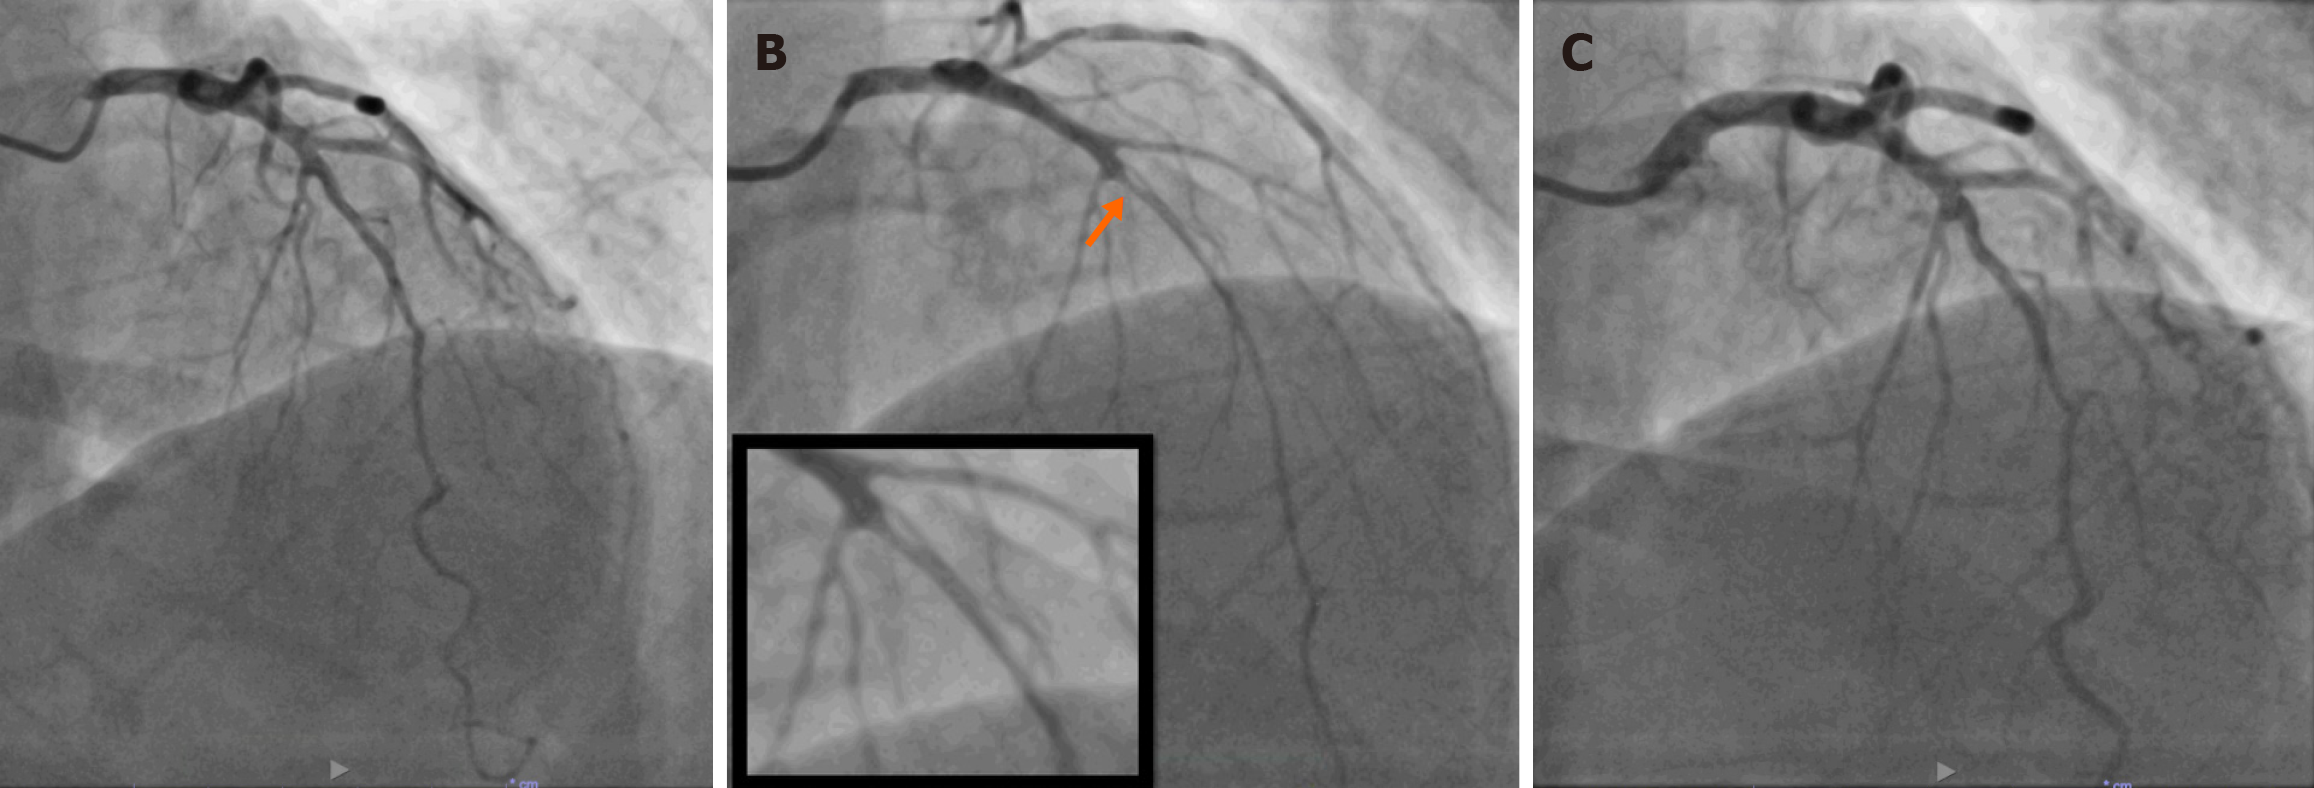

Figure 3 Positive acetylcholine provocation testing involving the mid-left anterior descending artery.

A: Baseline angiography; B: Significant vasospasm predominantly in the mid-left anterior descending artery region (orange arrow) with 50 mg of intracoronary acetylcholine; C: Reversal of vasospasm following 200 mg of intracoronary glyceryl trinitrate.